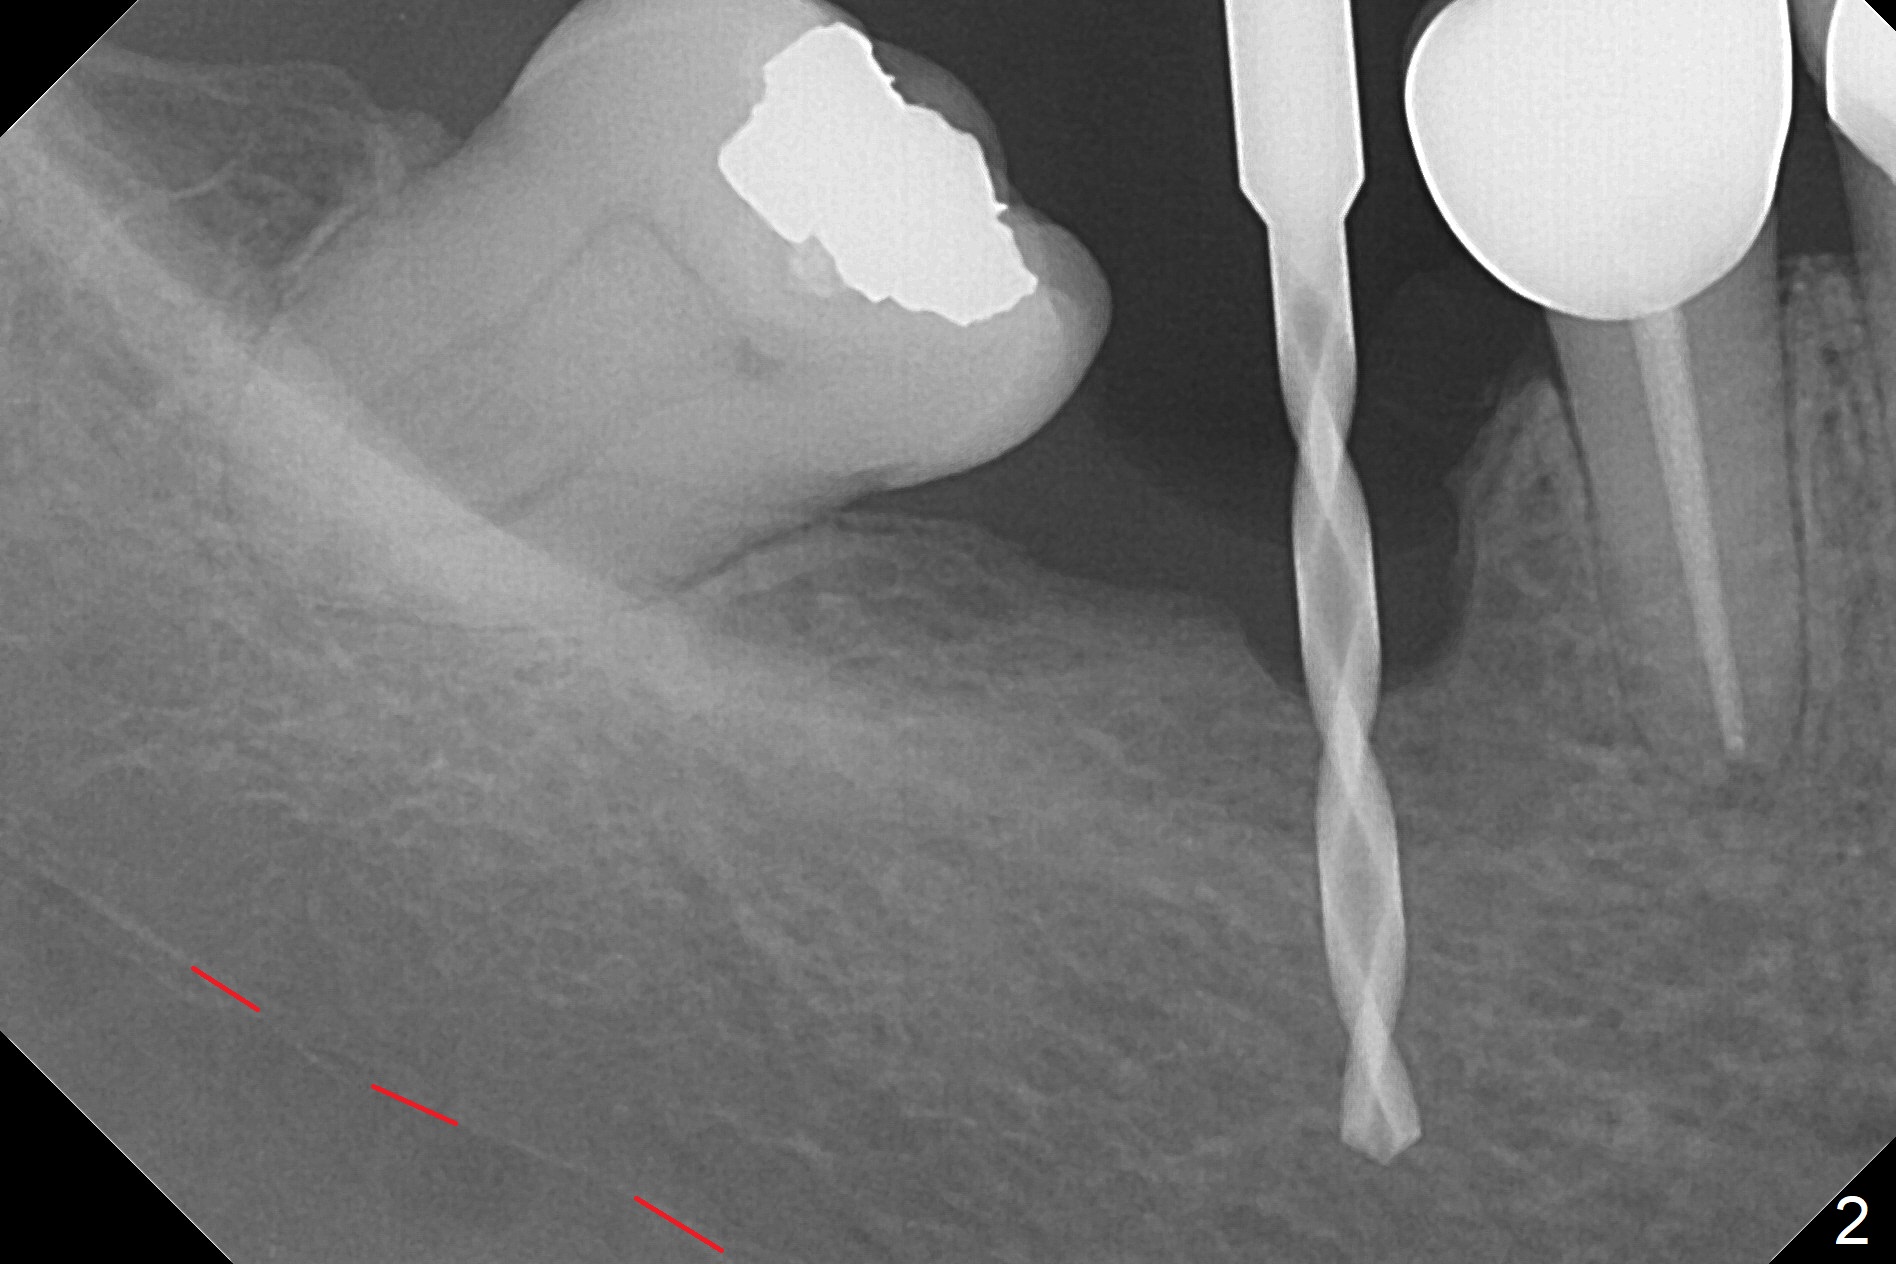

Incision reveals a narrow ridge and a narrow mesiodistal space at #30 (Fig.1).  It seems that a 1-piece implant is indicated.  Due to limited mouth opening, a 1.2 mm drill is unstable in place after use for 10 mm; instead a 1.5 mm drill is able to be inserted for 8 mm (Fig.2).  A 3x10(2) mm 1-piece dummy implant is placed with 40 Ncm at an apparently acceptable level (Fig.3 >).  Clinically a few threads are exposed buccally.  When a definitive implant with the same dimension is inserted with 45 Ncm, it looks seated too deep (Fig.4,5).  The latter is noted after suturing.  The implant is backed up for a few turns so that the length of the abutment appears a little more reasonable.  Introspectively, a 4 mm cuff should have been used after ridge reduction.  Although there is no bone loss 4 months postop (Fig.6), the abutment margin (Fig.7 arrow) is subgingival (red dashed line: gingival margin).  Diode laser is used for gingivectomy prior to impression.  The bone density around the implant increases 11 months post cementation (Fig.8 *), probably related to recurrent #18 infection.  The patient uses floss after meal.